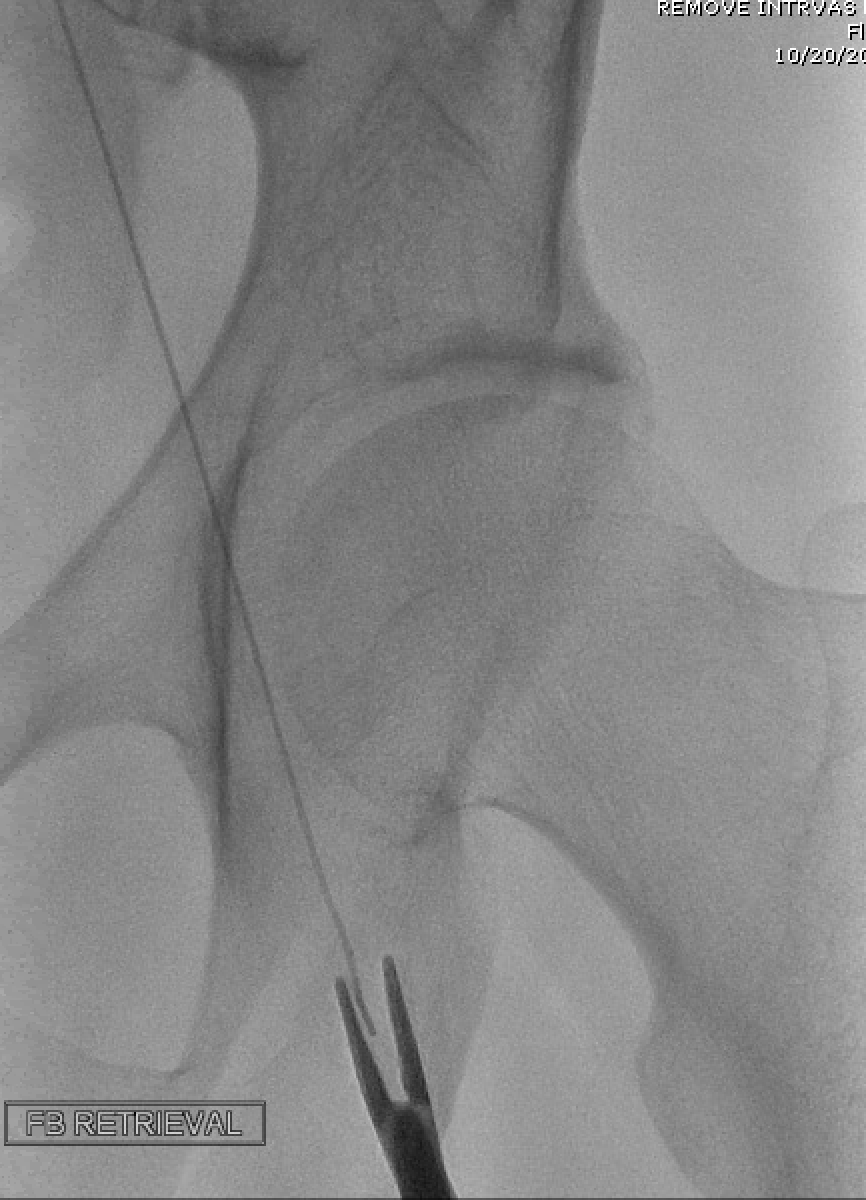

Despite appropriate antibiotics, he remained bacteremic. Suspicion for endocarditis was very high. On trans-thoracic and trans-esophageal echocardiograms (TTE and TEE, respectively), he had normal valves without vegetations, and a likely patent foramen ovale (PFO). Further imaging demonstrated a 40-cm-long metallic object running from his left femoral vein to the proximal IVC – likely a guidewire inserted and retained during treatment of his injuries in 2001. The patient underwent successful removal of the guidewire (image 2) and surgical treatment of multiple septic joints. Blood cultures subsequently cleared, and he was discharged with 6 weeks of intravenous antibiotics.